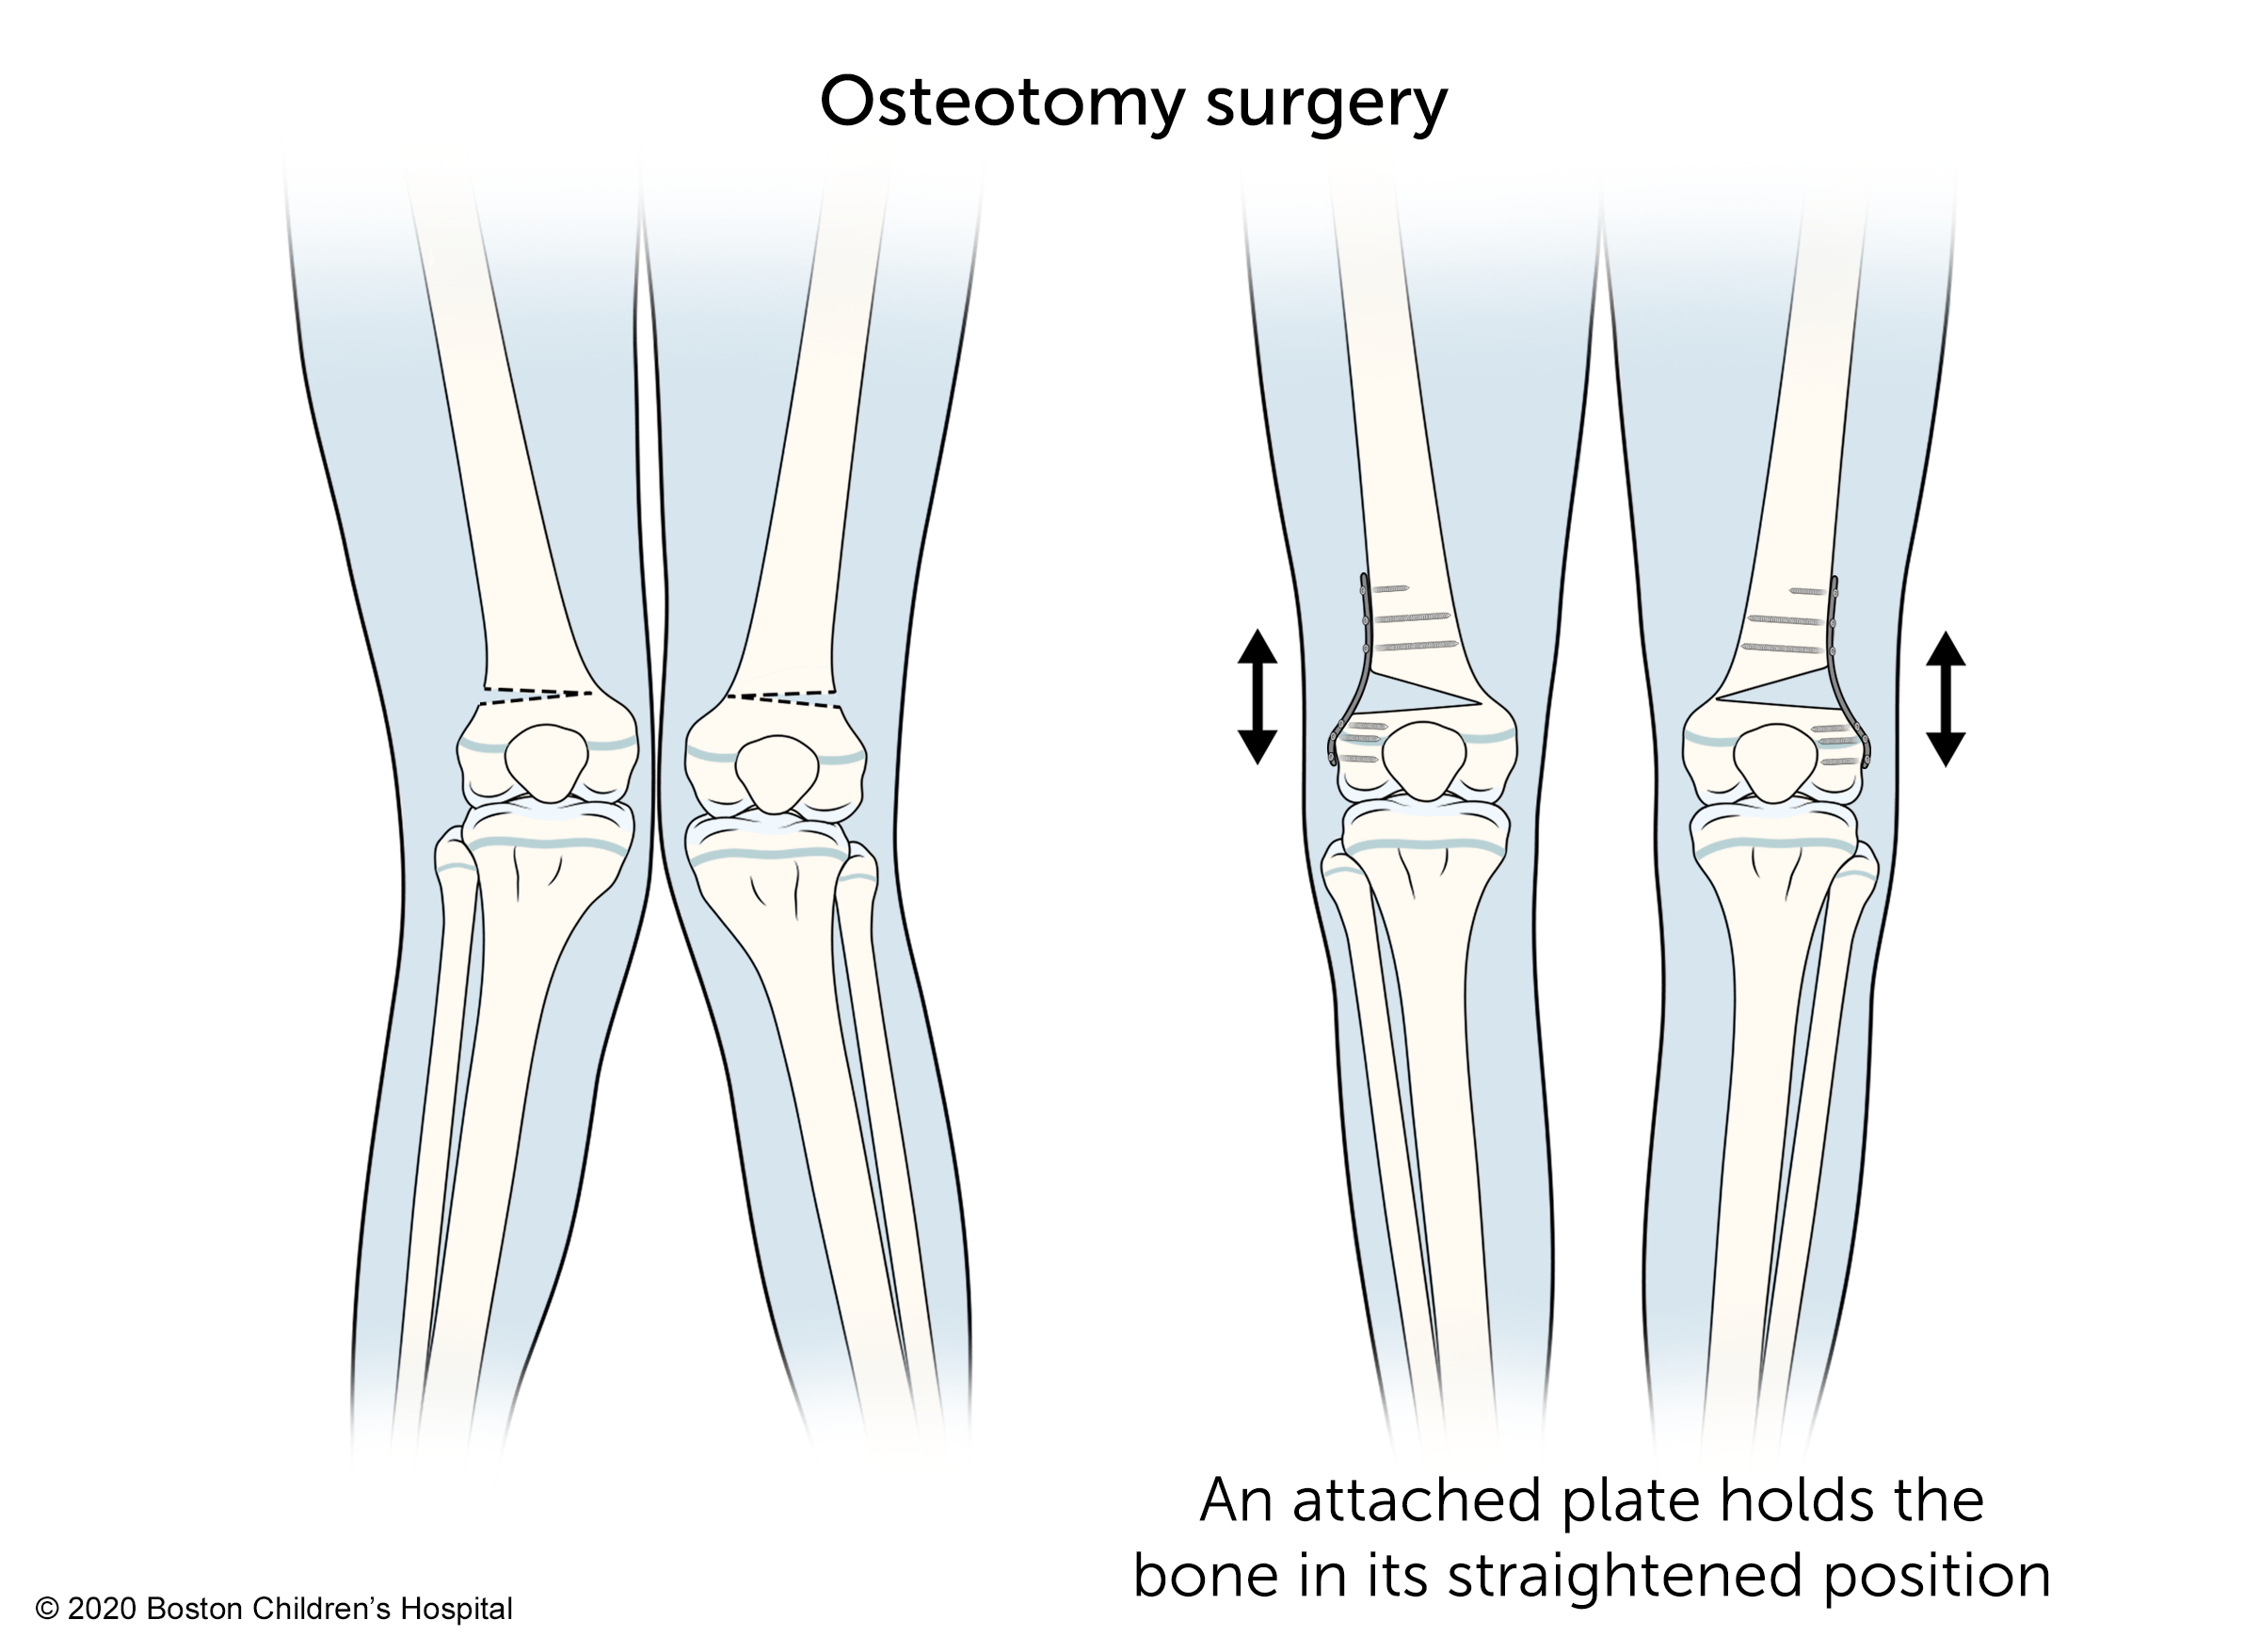

Osteotomy surgery

Osteotomy surgery can correct more severe deformities or knock knees that do not get better on their own by the time a child has finished growing. The goal of this procedure is to straighten the legs by changing the angle of the bones. A surgeon does this by cutting and realigning the bone above or below the knee.

Children typically stay in the hospital for a few days after osteotomy surgery. When they return home, they will need to limit weight-bearing activities and may need to use crutches or a walker for six to eight weeks. Physical therapy will help restore muscle strength. Typically, children can return to full activity, including sports, six months after the procedure.